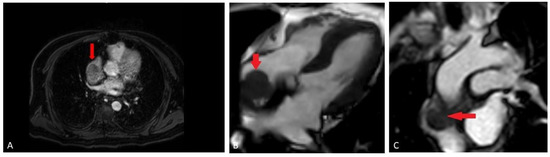

2. Case Presentation